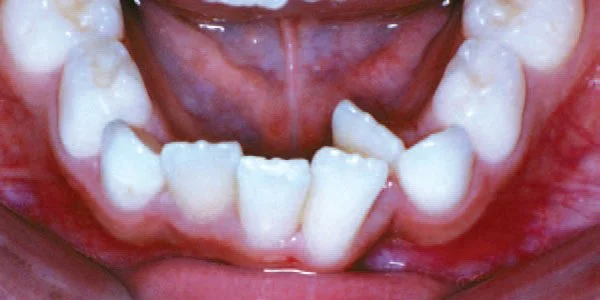

Crowding

Lack of space causes crowding as teeth erupt.